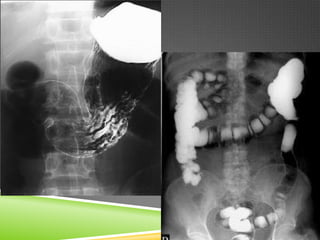

BARITADOS.

 Sal metálica.

 No se absorbe por vía gastrointestinal.

 No produce artefactos.

 Eliminación en las heces fecales.

 Grado de excreción en función del tránsito GI.

 Tiende a sedimentarse.

BARITADOS.  Sal metálica. No se absorbe por vía gastrointestinal.  No produce artefactos.  Eliminación en las heces fecales.  Grado de excreción en función del tránsito GI.  Tiende a sedimentarse.